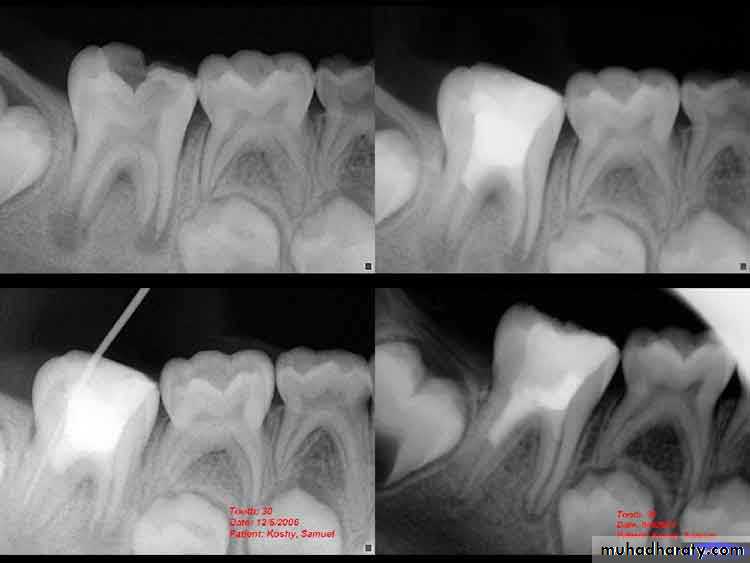

MTA was introduced to endodontics by Lee et al. in the early 1990s. This bioactive silicate cement was originally composed of tricalcium silicate, tricalcium aluminate, tricalcium oxide, silicate oxide, and other mineral oxides. Originally a gray powder, white MTA was produced for esthetic reasons.Comparison of dentin bridge formation using mineral trioxide aggregate (MTA) or calcium hydroxide in dog pulps.A,After 1 week, a noticeable bridge has formed subjacent to MTA.B,A comparable bridge under calcium hydroxide after 2 weeks.C,A 4-week specimen with MTA shows excellent bridge formation.D,Consistently, the bridge formation under calcium hydroxide lagged behind MTA; an example of bridge formation under calcium hydroxide after 8 weeks. CH = calcium hydroxide; DB = dentin bridge; MTA = mineral trioxide aggregate.